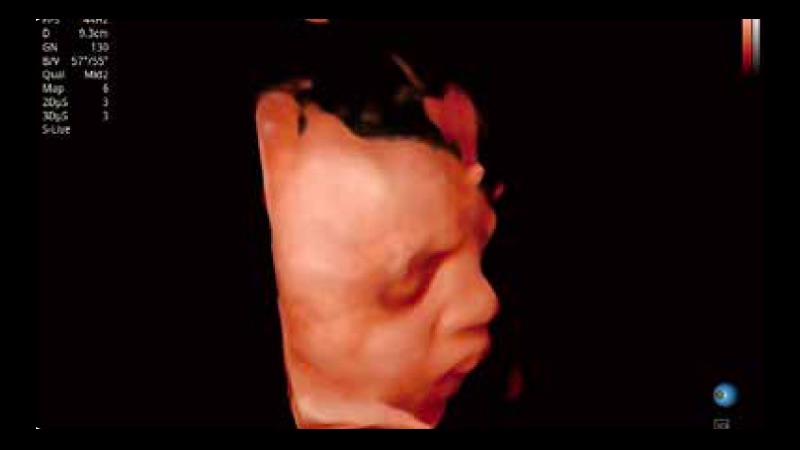

凭借开立医疗先进的成像技术和优异的探头技术提供的清晰的图像表现,您可以更自信地做出临床决策。